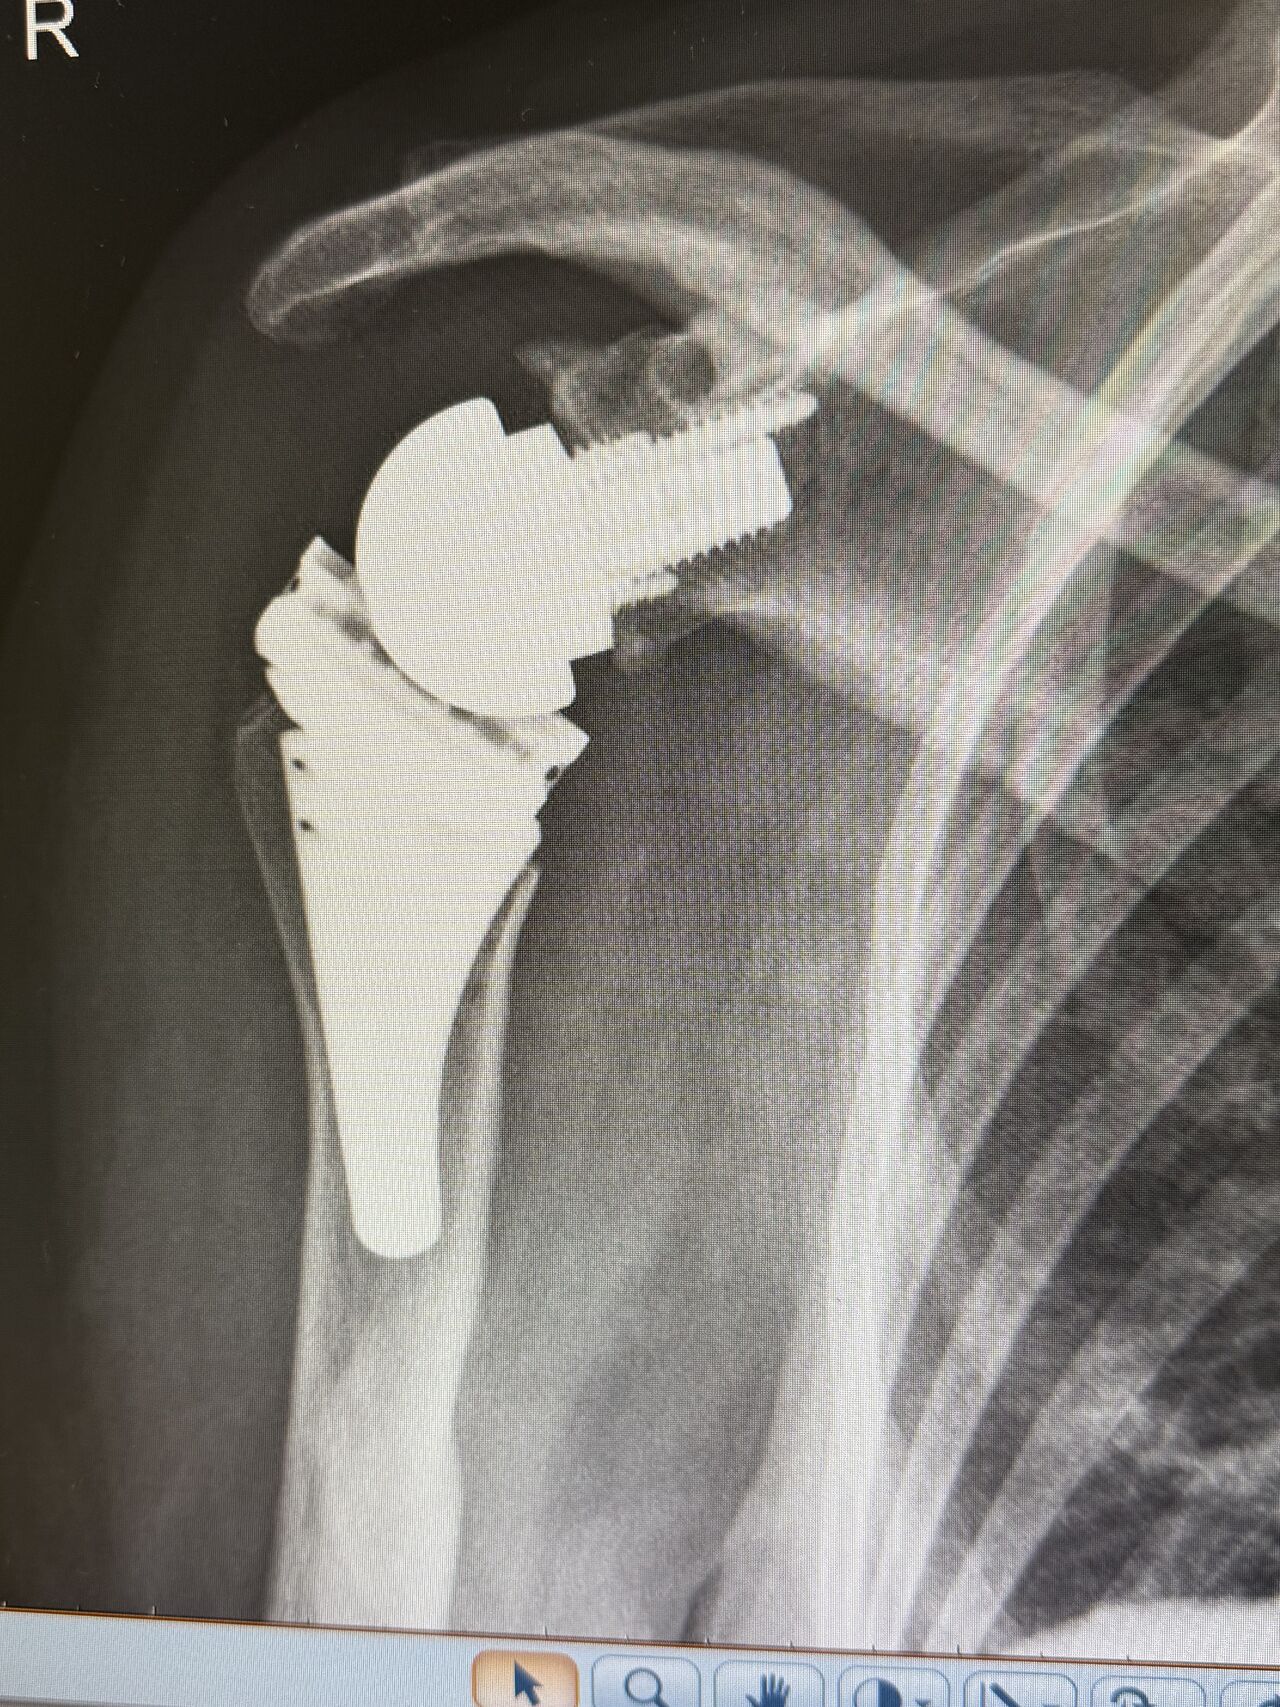

No último dia 6 de janeiro, fomos pioneiros em Portugal com a primeira artroplastia reversa do ombro com haste curta. O sistema Virtual Implant Positioning, desenvolvido pela Arthrex GmbH, permite um posicionamento individualizado e pré-planeado do pino guia da glenóide, permitindo prever o tamanho do implante, o posicionamento e a amplitude de movimento prevista, entre outras características incríveis. É uma ferramenta indispensável para todas as artroplastias do ombro, reduzindo o tempo de operação, aumentando a previsibilidade e a precisão, melhorando os resultados e reduzindo as complicações.